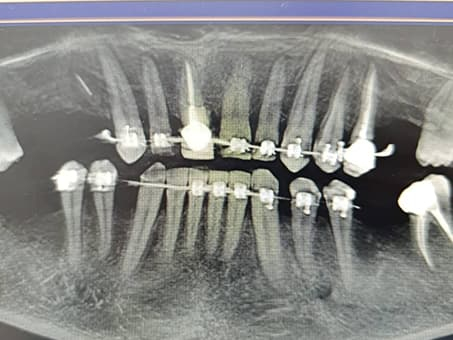

1. Диагностика

Тщательный осмотр и 3D моделирование строения нужного участка ротовой полости. Данная процедура проходит при помощи лучшего в Казахстане томографа немецкой фирмы Sirona.

Компьютерная диагностика на начальном этапе лечения позволяет врачу детально представить состояние и количество костной ткани, особенности строения ротовой полости пациента, а также вовремя выявить скрытые заболевания — кисты, гранулемы и пр.

Трехмерное моделирование позволяет правильно рассчитать расположение будущих имплантатов и буквально до микрона определить угол вхождения штифтов в челюсть.

4. Имплантация

Это основной этап. Основной этап также делится на 2 этапа — хирургический и ортопедический. На первом этапе имплантации зубов происходит установка выбранных имплантатов в костную ткань и контроль над процессом выздоровления. На втором (ортопедическом) этапе, изготавливается коронка и устанавливается на хорошо прижившийся стержень. Рассмотрим процесс имплантации зубов детальнее:

Хирургический этап: установка импланта

На этом этапе имплантации зубов титановый имплант вживляется в костную ткань под местной анестезией. Процедура занимает в среднем 30–60 минут и проходит безболезненно. После установки начинается процесс остеоинтеграции — срастания импланта с костью, который длится в среднем от 2 до 3 месяцев.

Наши работы